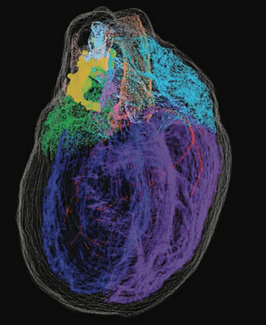

The normal functioning of our hearts is maintained by the brain via an intricate network of nerves. As an added layer of safety, the heart has its own ‘little brain’, called the intracardiac nervous system (ICN) to monitor and correct any...